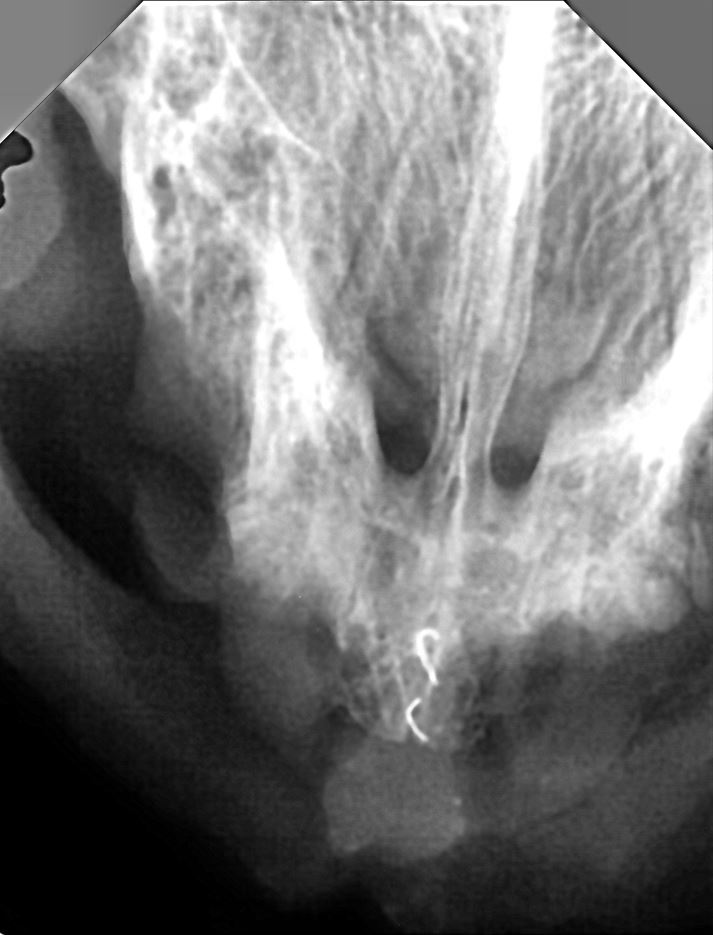

| 치료과정 | 수술전 계획은 송곳니는 살릴수 있으면 살려서 치료후 제자리방사를 할 계획을 가지고 있었습니다.의사선생님께서 엑스레이 검사를 해보고 결정해야 한다고 하셨고 결과는 좋지 않았습니다.어금니쪽 턱뼈가 녹아 있고 송곳니도 염증이 심해 살릴수 없으며 부러진 이도 있고 목구멍 근처까지 염증이 번지고 있는상태라고 아주 나쁜 상태라고 하셨습니다.할수없이 전발치를 해야하는 상황이었습니다.전발치후 방사는 안될거라서 동물등록도 같이 했습니다.수술이 오래걸렸고 수술후 꼬질이를 보니 염증이 심해서 피를 많이 흘렸다고 하셨는데 얼굴이고 이마나 몸에 피가 많이 뭍어있는것을 보니 더 안스럽고 애처로윘습니다.저래가지고 언제 회복하나 걱정도 됐습니다.구내염도 LPGS인거 같다고 하셨고 치료기간을 오래봐야 한다고 하셨습니다.약을 1주일치를 받아집으로 데려와서 케이지에 방석을 깔고 이불을 덮어주고 그렇게 거의 하루를 있었던거 같습니다.하루지나고 나서 사료를 불려서 곱게 갈고 좋아하는 캔에 비벼서 주니 잘먹어서 안심이 돼습니다.수술후 5일 정도까지는 그렇게 먹고 자고 화장실가고 누위만있었는데 차츰 기운이 차려지는것이 눈에 보였습니다.일주일 후에 다시 약을 단계를 낮추어서 조제해주셨고 밥을 안먹 거나 힘들어 할때만 먹이라고 하셨는데 그후로 3일정도 먹고 남겨둔 상태입니다.밥을 잘 먹고 케이지에서 나와서 방안 생활도 아주 잘 적응해서 방문에 네트망을 해서 집에 있던 냥이들과 서로 얼굴익히가를 하게 하고 했습니다.꼬질이는 어디 집냥이 였든것이 아닌가 싶게 친화적인 아이입니다,만져주면 더 만지라고 비벼대고 솔질을 해도 좋아합니다.그리고 다른고양이 보고 경계를 안합니다.오히려 저희 예민냥들이 까칠하게 굴어도 무시하고 지나갑니다. |